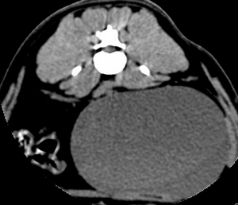

L4-L5 右侧椎间孔狭窄 L5-L6 双侧椎间孔狭窄

CT横断扫描图上可见分别在L4-L5、L5-L6、L7-S1处椎间盘突出,压迫硬囊膜和椎间孔,导致相应的椎间孔狭窄,椎间孔内的神经受到压迫,导致该犬后肢无力及尿潴留。